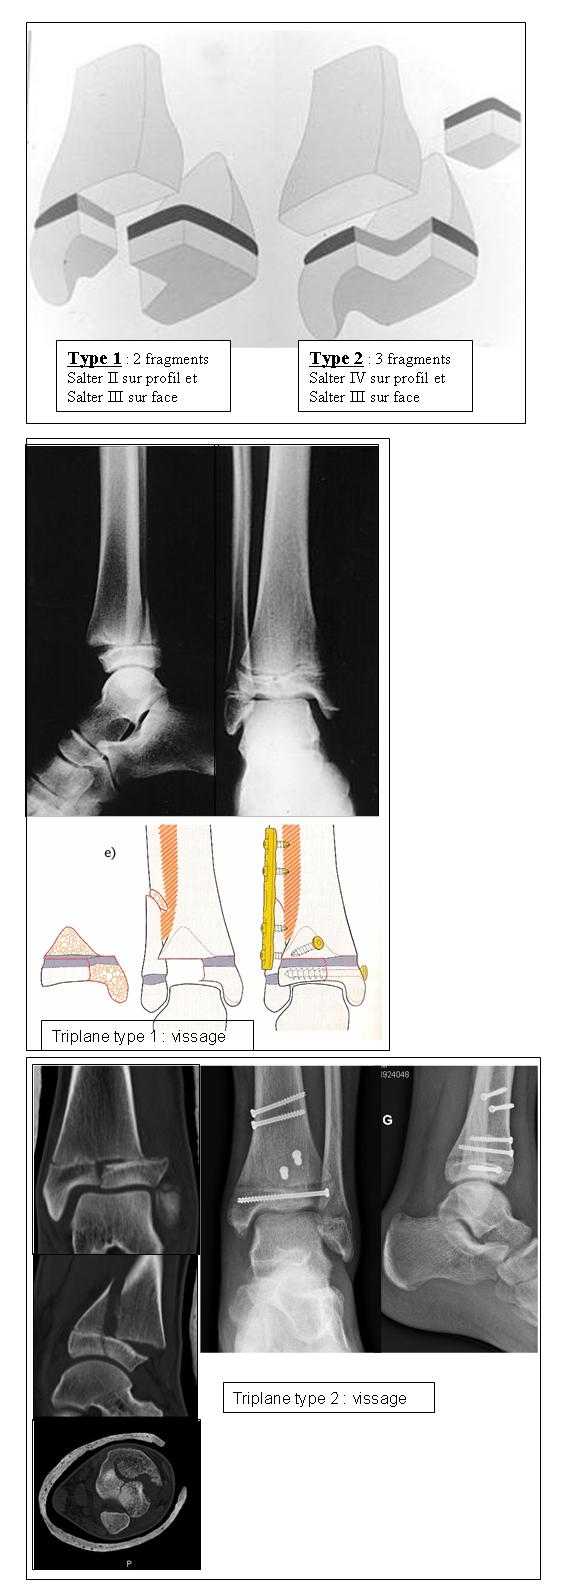

◦ type 1: triplane à 2 fragments

▪ ressemble à un Salter II sur le profil

▪ et à un Salter III sur le face

◦ type 2: triplane à 3 fragments

▪ ressemble à un Salter IV sur le profil

Traitement:

si < 2 mm: R/ orthopédique possible mais surveillance de près pour déceler un déplacement

si > 2 mm: R/ chirurgical (réduction ouverte et ostéosynthèse)